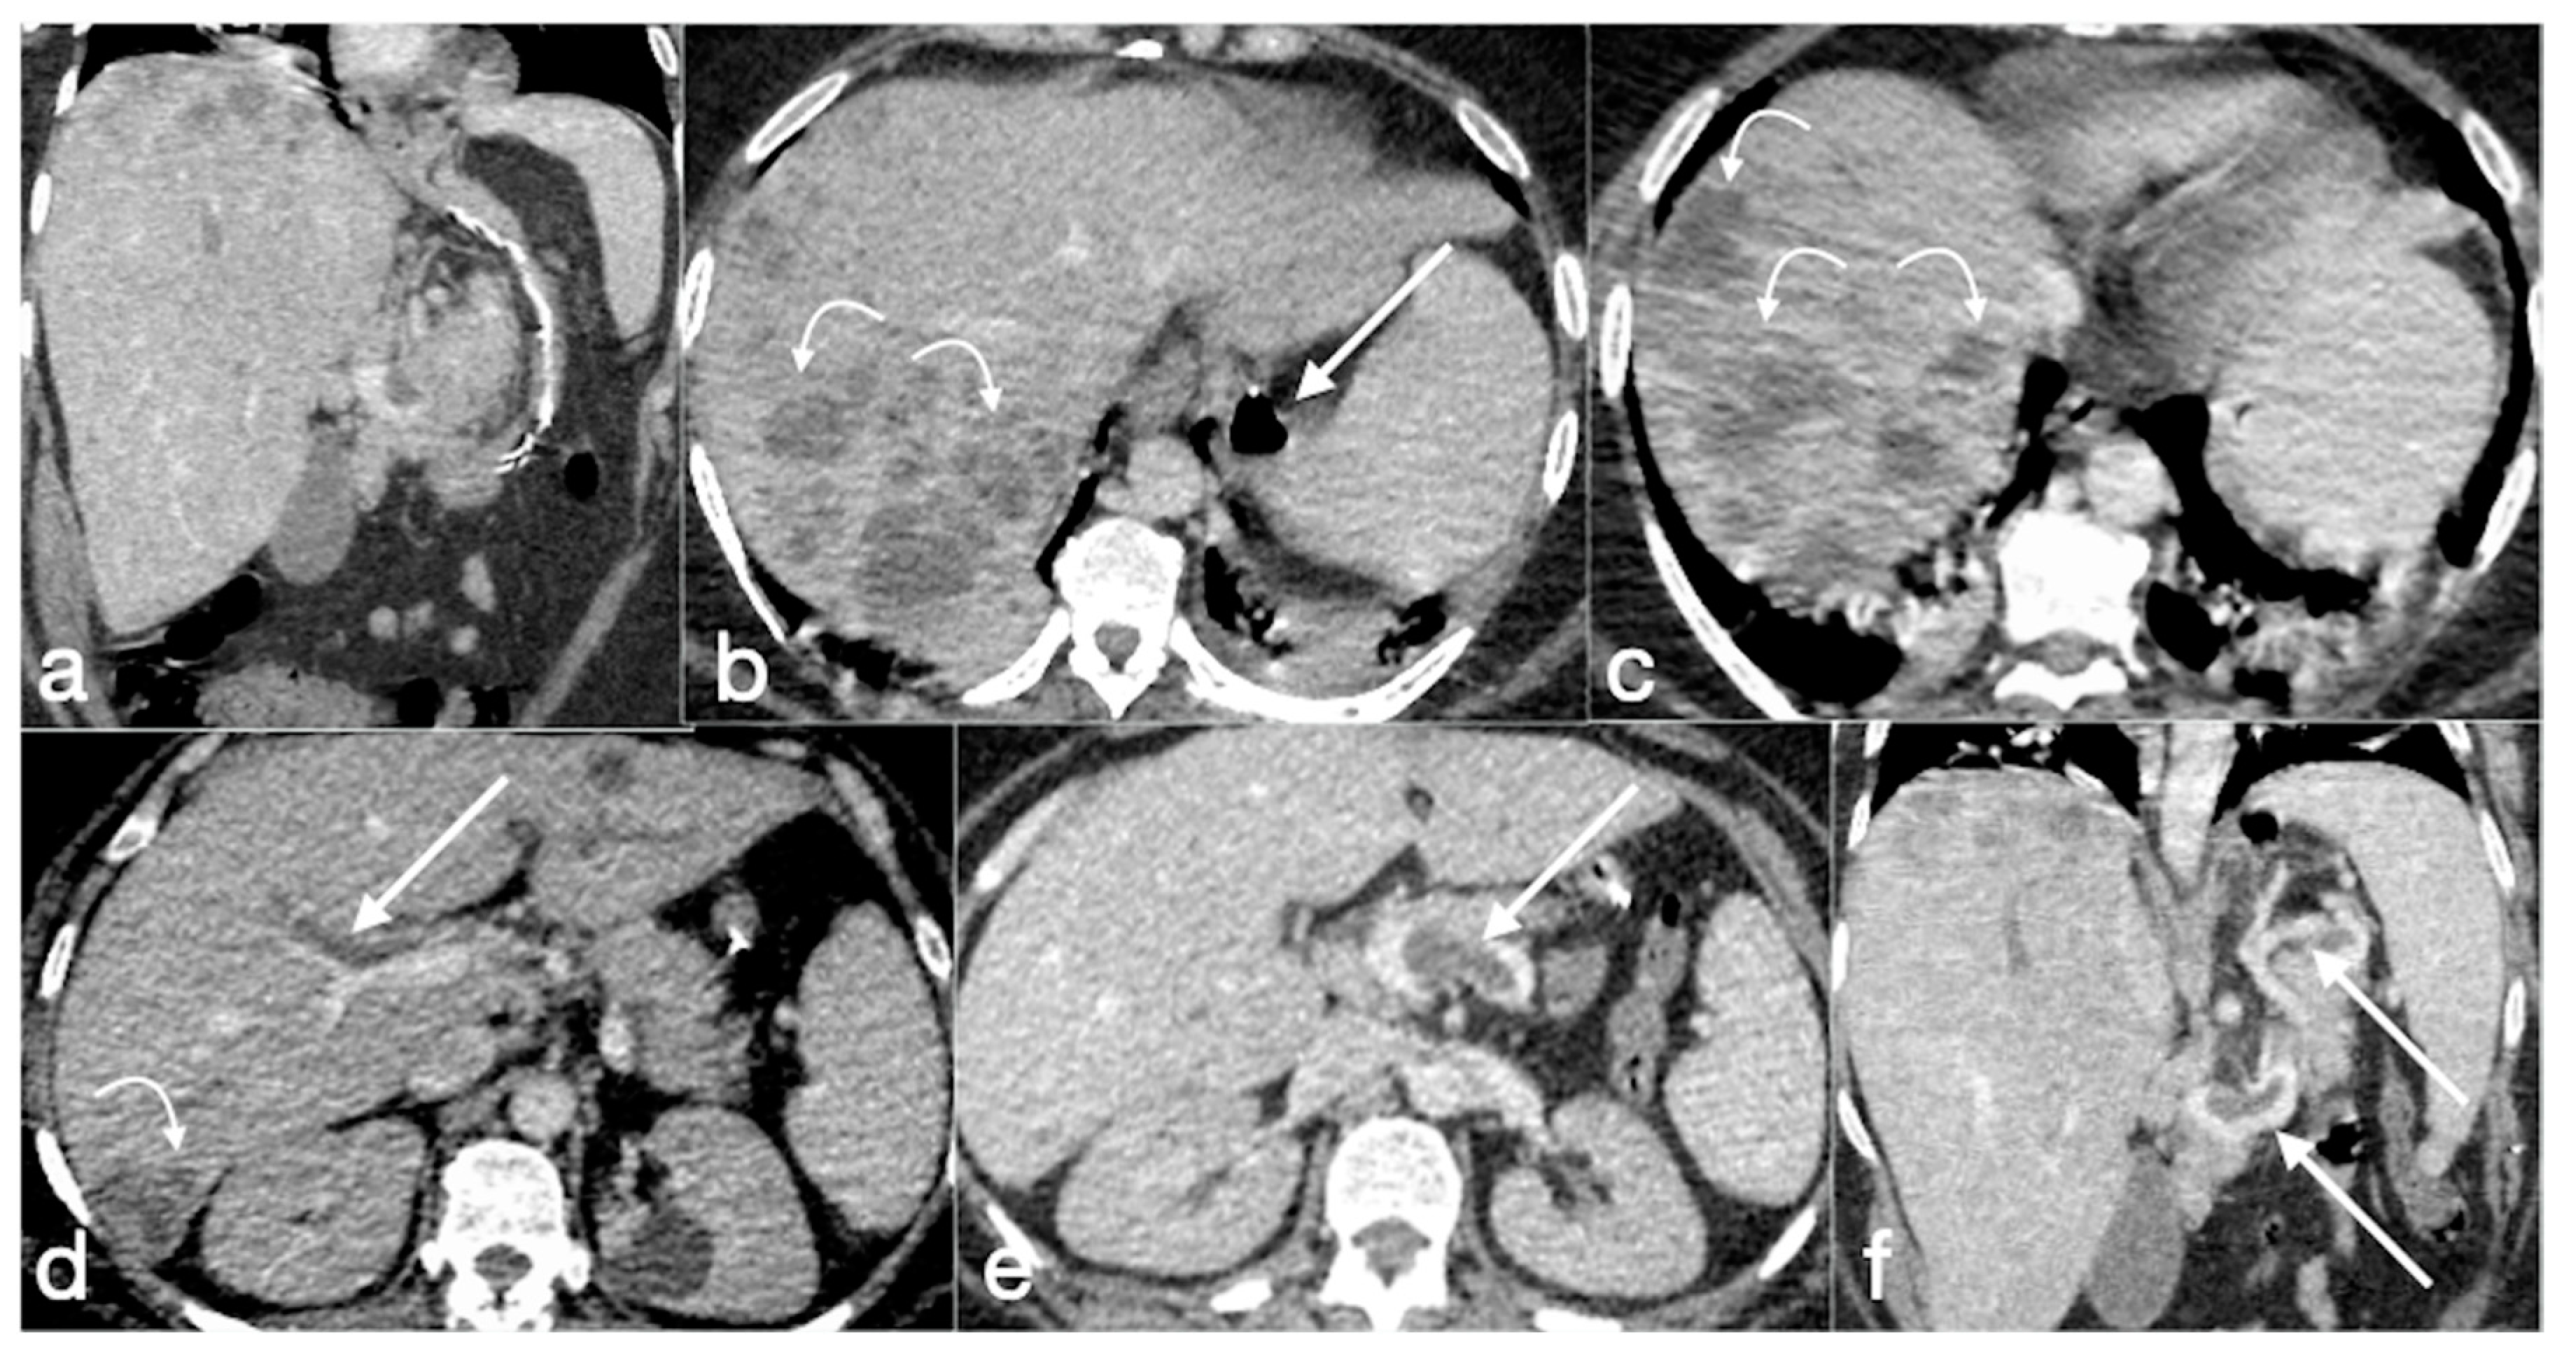

3.3.4. RYGB

- Stenosis

- Leak

- Small bowel obstruction

- (a)

- The obstruction involves the alimentary limb, that appears dilated, while both biliopancreatic limb and distal common channel are hypotonic.

- (b)

- The obstruction involves the biliopancreatic limb, which appears dilated, whereas the alimentary limb and distal common channel are decompressed. This closed-loop obstruction could determine perforation of excluded gastric cavity. On UGI, there is a dilated and fluid-filled limb (biliopancreatic) excluded by an oral contrast passage that could determine a mass-effect on the other bowel loops. Upon CT, detection is easy, and it should be suspected not only for the biliopancreatic limb appearance associated to decompression of alimentary and common channel, but also for the recognition of dilatation of excluded gastric room.

- (c)

- The obstruction involves the common channel; any bowel loops upstream appear dilated [4].

- Fistula

- Internal hernia

- Marginal ulcers

- Intussusception